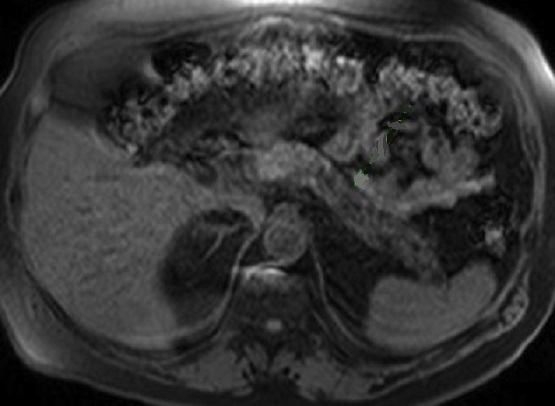

Aspect

radiologique de dfilatation/stenose du canal

pancreatique principale d'une pancreatite chronique

avancee tardive ( fleche rouge ) .Image IRM encoupe

axiale a ponderation sur T2 . Parenchyme du pancreas

est atrophique et hyperintense .. |